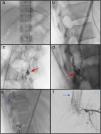

Presentamos el caso de una mujer de 31 años remitida a nuestro departamento con una paraparesia asimétrica progresiva de 10 meses de evolución y disfunción vesical ocasional. Con el diagnóstico de malformación arteriovenosa espinal de tipo IV, se realizó una embolización programada tras la que se produjo una hemorragia subaracnoidea masiva debido a la laceración de la arteria espinal anterior que precisó una craniectomía bifrontal urgente. Discutimos el papel del neurocirujano en el tratamiento de las complicaciones derivadas del tratamiento endovascular de la patología espinal.

We reported a 31 years old female referred to our department with progressive asymmetric spastic paraparesia for 10 months of evolution and occasional bladder dysfunction. With the diagnosis of a type IV arteriovenous malformation, a scheduled embolization was performed resulting in a massive subarachnoid hemorrhage due to the ASA laceration requiring an emergency bifrontal craniectomy. We discuss the neurosurgeońs role in complications during endovascular spinal vascular pathology treatment.